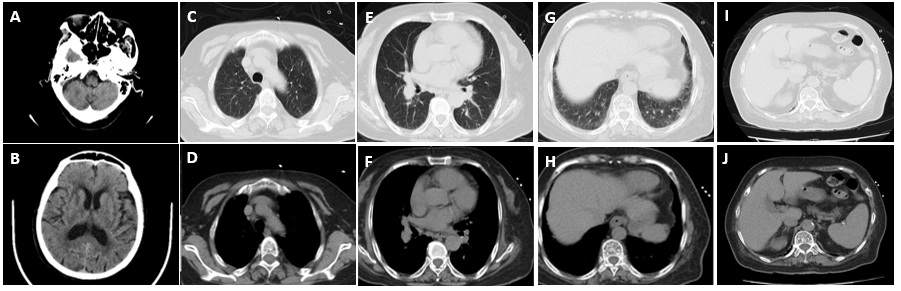

35cm致命栓子惊现肺动脉!看介入治疗如何破解中高危肺栓塞救治困局

病史摘要:43 岁男性,主因进行性加重的呼吸困难和咯血于外院就诊。既往史未提及,现病史为出现上述症状后于外院检查,生命体征提示血压 110/60 mmHg,心率 117 次/分,辅助供氧下氧饱和度 90%,呼吸频率 27 次/分。 诊疗过程:外院超声心动图显示右心室扩张,CT 肺血管造影提示急性肺栓塞累及主肺动脉及其分叉处,高敏心肌肌钙蛋白 I 升高,被归类为中高风险,初用低分子肝素治疗